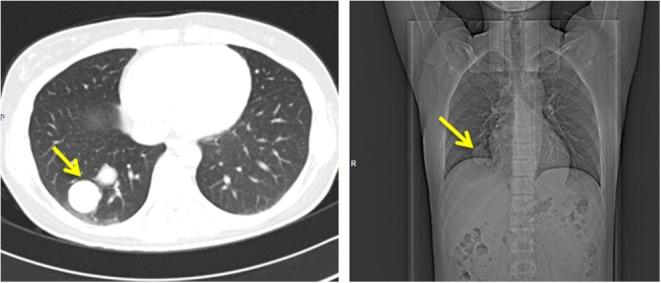

Parathyroid carcinoma is an extremely rare disorder with little treatment options. It could be misdiagnosed in medical centers with little experience in management of such cases. Our clinical case shows that the initial misdiagnosis of a parathyroid carcinoma in a young woman has led to the development of multiple lung metastases, thus making its treatment hardly possible. Initiation of treatment with sorafenib - a multi-kinase inhibitor approved for treatment of different types of cancer but not parathyroid carcinoma - has led to a significant decrease in the size of lung metastases and has prevented the progression of hyperparathyroidism, which is usually severe in cases of parathyroid carcinoma. The detection of a germline mutation in this patient has raised additional concerns about the necessity of periodic screening for early detection of renal, jaw and uterine lesions.

甲状旁腺癌是一种极其罕见的疾病,治疗选择有限。在处理此类病例经验不足的医疗中心,它可能会被误诊。我们的临床病例显示,一名年轻女性甲状旁腺癌的初始误诊导致了多处肺转移的发生,从而使其治疗几乎变得不可能。使用索拉非尼(一种被批准用于治疗不同类型癌症但未被批准用于甲状旁腺癌的多激酶抑制剂)进行治疗,已导致肺转移灶大小显著减小,并阻止了甲状旁腺功能亢进的进展,而甲状旁腺癌患者的甲状旁腺功能亢进通常较为严重。该患者种系突变的检测引发了对定期筛查以早期发现肾脏、颌骨和子宫病变必要性的更多关注。